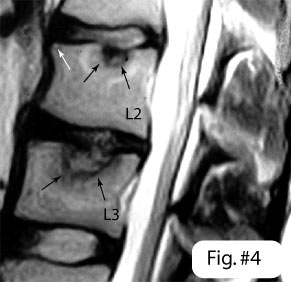

I piatti vertebrali sono la superficie sopra e sotto delle vertebre, in pratica il tetto e il pavimento, sono i dischi tra le vertebre che li sfondano, in seguito a sovraccarichi meccanici prolungati.

Un signore dal cognome molto lungo1 ha trovato che su 692 discografie,(iniezione di mezzo di contrasto nel disco inter vertebrale) in 14 il mezzo di contrasto finiva nel corpo inter vertebrale (evidenza di frattura del piatto).

Iniettando il mezzo di contrasto in questi dischi, tutti i pazienti proprietari dei dischi ebbero dolore e 9 di loro ebbero il dolore che avevano descritto all’inizio.